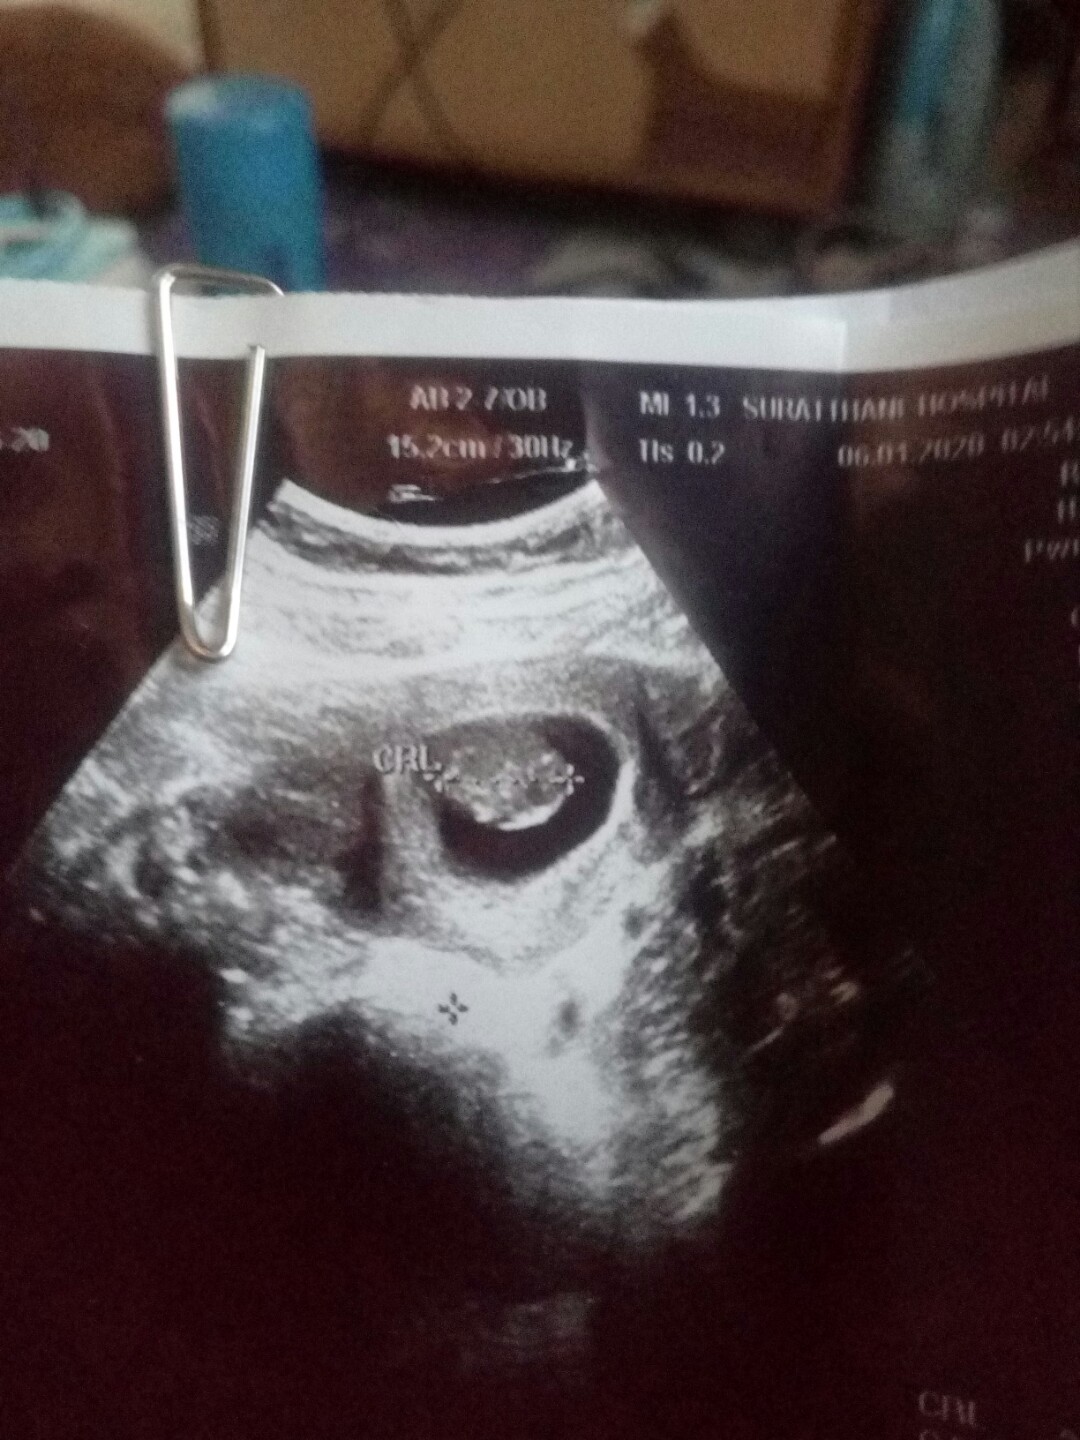

ตอนนี้ท้องได้ประมาน 6วีคแล้วค่ะ ไปซาวด์หมอเจอแต่ถุงตั้งครรภ์ยังไม่เจอตัวอ่อน ปกติกี่วีคถึงจะเจอตัวอ่อนค่ะ